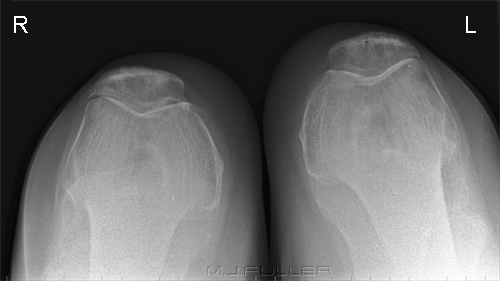

What does this x-ray show?

Bilateral skyline view- to show orientation